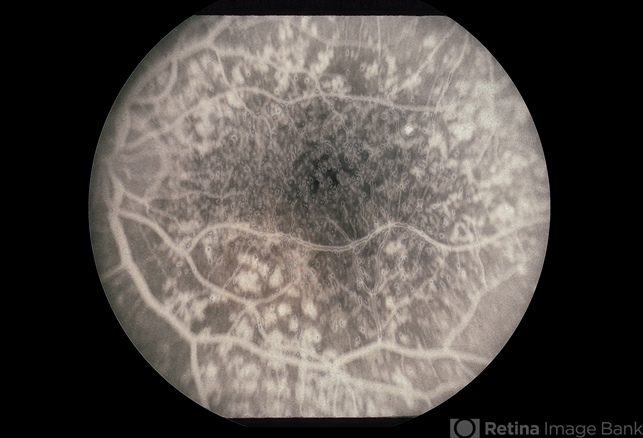

- cuticular drusen

- Cuticular drusen.